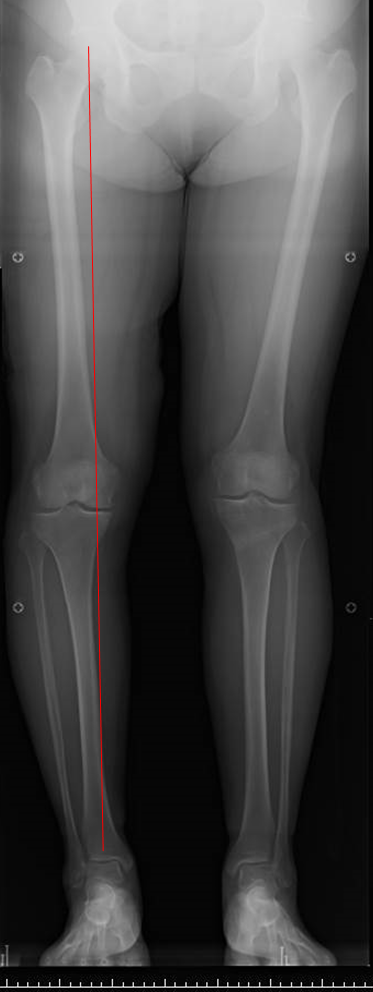

変形性膝関節症の多くは、膝がO脚であるために膝の内側の軟骨が減ることで痛みが生じます。

すねの骨(脛骨)を切って、少しX脚に矯正する手術です。

この手術を行うと膝の内側にかかっていた体重が膝の外側にかかるようになり、痛みが軽減または消失します。